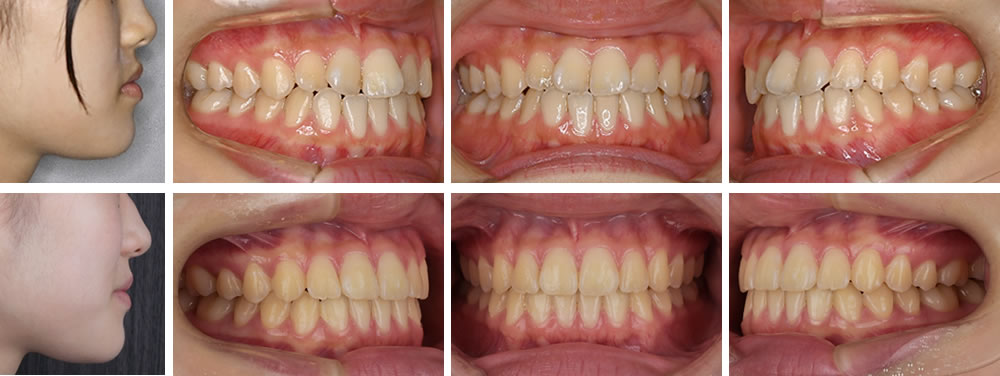

叢生(デコボコ歯列)の歯列の矯正治療ビフォーアフター写真と解説 治療の詳しい解説 10代の女性です。前歯の歯並びが気になる。右の前歯が反対になっていて引っかかることを主訴に来院されました。分析の結果、叢生という状態でなる […]